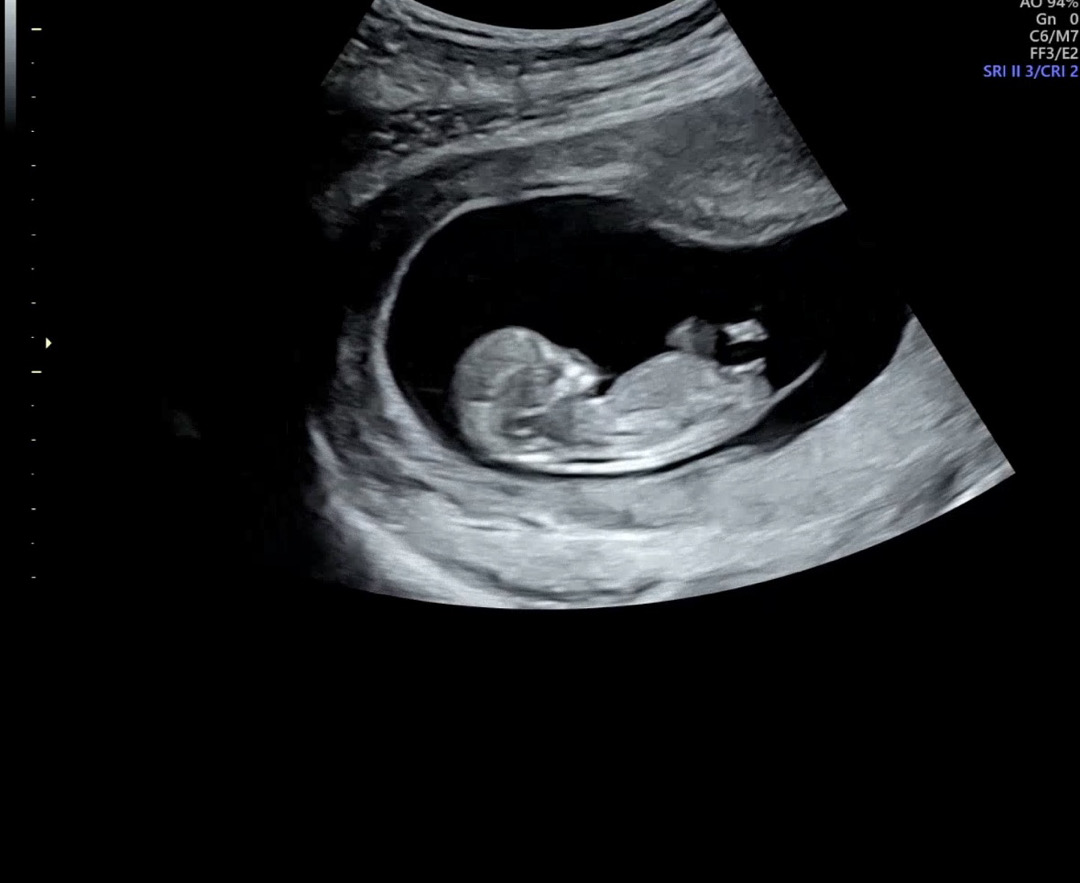

11주 각도법

11주라 좀 이르긴하지만 각도법 잘보시는분 투표 부탁해요!